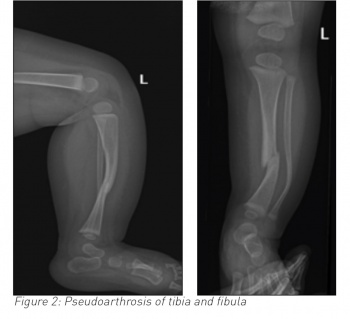

• An eight-month-old non-mobile female infant presented with a history of not moving her left leg for two days and displayed discomfort on passive movement of her left foot. She underwent an x-ray of her left leg, revealing fracture of both tibia and fibula along with antero-lateral bowing. It was strongly considered for her to have a non-accidental injury (NAI). She underwent further tests to investigate the non-accidental injury and had her fracture splinted.

Long bone dysplasia, almost always unilateral occurs in 3-5% of individuals with NF-1.2 The tibia is the most commonly affected long bone, often in association with the fibula. Once the long bone fractures, non-union (pseudoarthrosis) frequently occurs. The shortening of the affected limb occurs in younger patients because of tibial bowing and poor growth in distal tibial epiphesis.3,4

Pseudoarthrosis of the tibia and fibula

Treatment of pseudoarthrosis of long bone is still a challenge. Each treatment aims to obtain a long-term bony union of dysplastic fracture site to prevent limb length discrepancy, to avoid soft tissue lesions and associated joint stiffness. An invasive method of treatment comprises stable internal or external fixation of pseudoarthrotic site with a bone graft. A noninvasive method, which includes electrical stimulation without surgery, is also described to enhance union. However, neither has yet proven its superiority.4